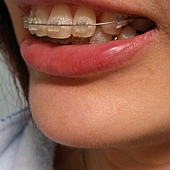

莎莎第三次回診是201314,

距離之前2012/10/19戴上矯正器已經兩個半月,

下排已經從內凹變成完全的圓弧型了,

速度真的很快,

現在他可是對我牙齒的整齊讚譽有加,

莎莎很高興,

這兩個半月的辛苦是值得的